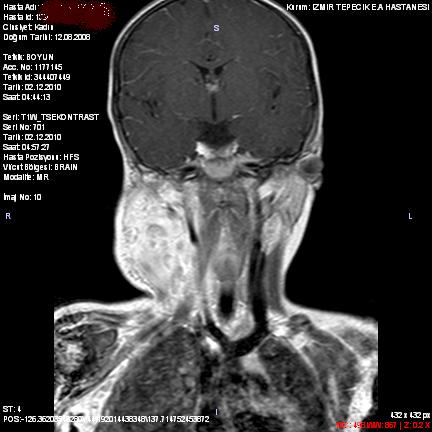

Cervical Lymphadenitis Due to Nodular Fasciitis in a Child

Nodular fasciitis is a benign, reactive proliferation of fibroblasts in the subcutaneous tissues. It usually affects the trunk and upper extremities, and rarely the head and neck region of young adults. It is rare among children and the histologic findings may incorrectly suggest malignant lesions. We describe a two-year-old girl that referred to our clinic with complaints of fever and swelling on the right side of neck and diagnosed as lymphadenitis clinically. Cervical lymphadenitis due to nodular fasciitis is a rarity. We emphasize that nodular fasciitis needs to be included in the differential diagnoses of neck lymphadenitis during childhood.